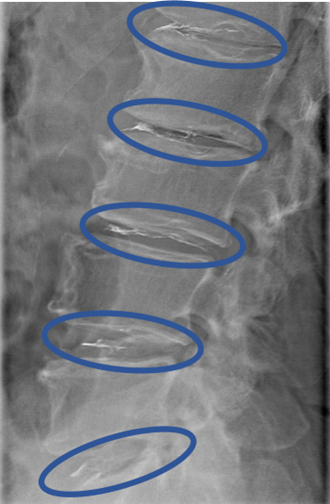

DiscoGelを入れた後の画像になります。

治療は 50分程度で終了

回復室で休憩後、歩いて帰院されました。